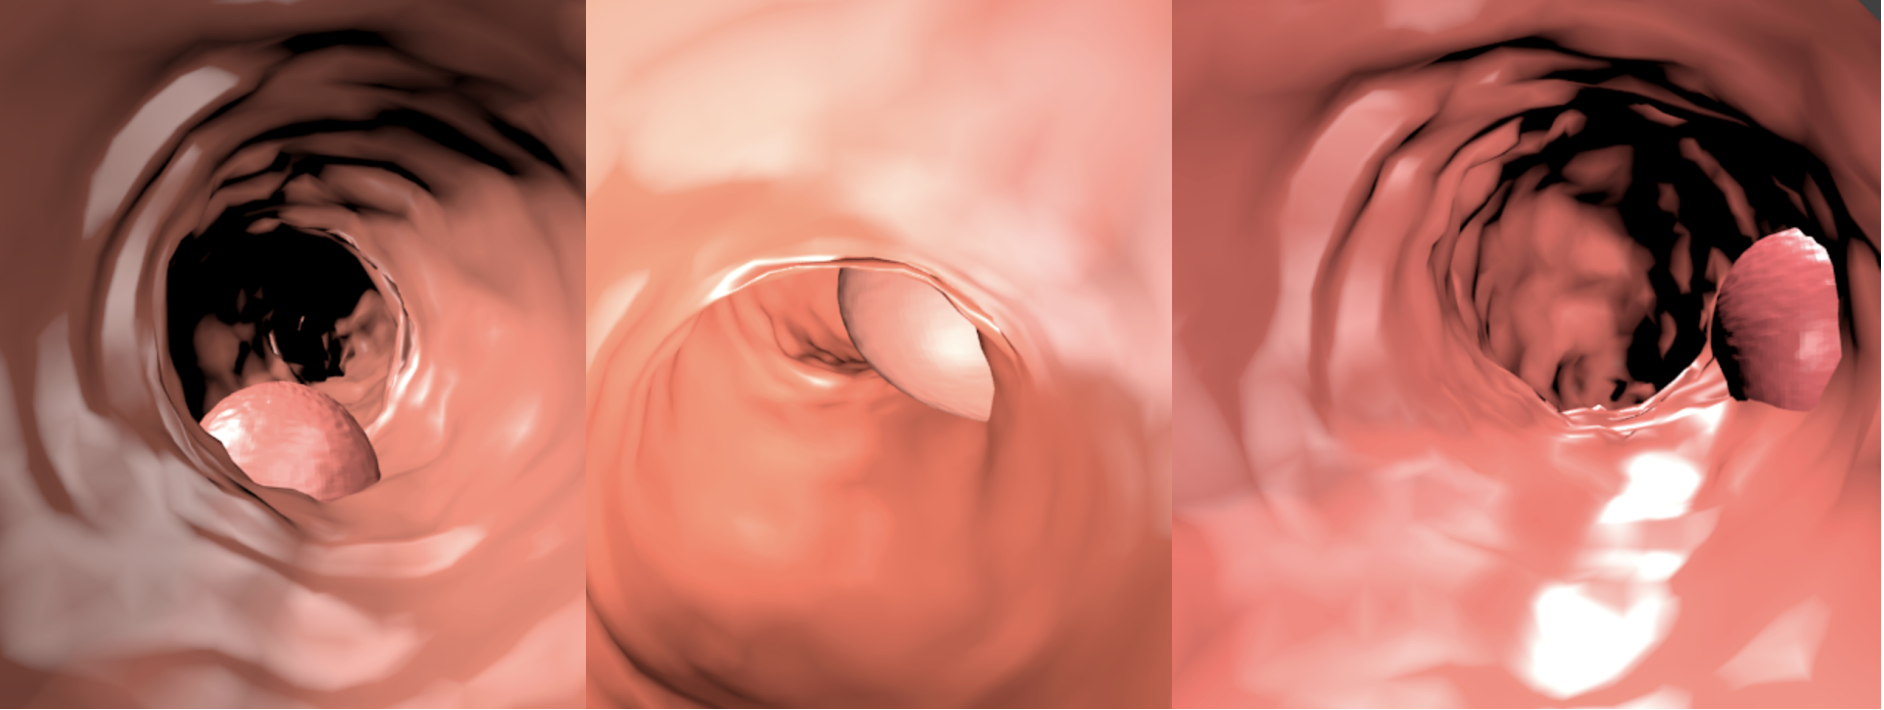

Train data: Synth-colon

• 828 images

• 256x256 pixels

• Generated with Blender

Enric Moreu, Kevin McGuinness, and Noel E O’Connor. “Synthetic Data for Unsupervised Polyp Segmentation”. In: Irish Conference on Artificial Intelligence and Cognitive Science (AICS). 2021.

Synthetic

Real

Domain randomization